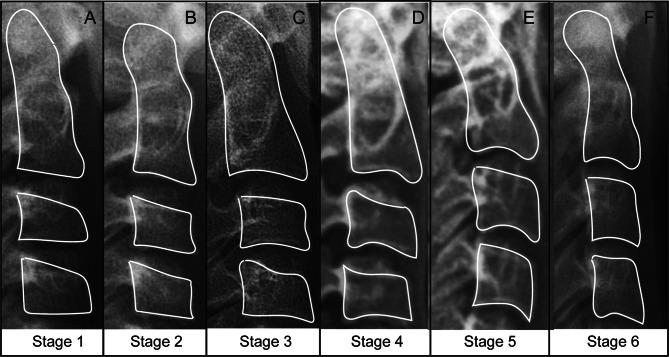

A total of 560 female cephalograms were collected, and cephalograms with unclear vertebral shapes and deformed scales were removed. 480 films from female adolescents (mean age: 11.5 years; age range: 6-19 years) were used for the model development phase, and 80 subjects were randomly and stratified allocated to the validation cohort to further assess the model's performance. Derived significant predictive parameters from 15 anatomic points and 25 quantitative parameters of the second to fourth cervical vertebrae (C2-C4) to establish the ordinary logistic regression model. Evaluation metrics including precision, recall, and F1 score are employed to assess the efficacy of the models in each identified cervical vertebrae maturation stage (iCS). In cases of confusion and mispredictions, the model underwent modification to improve consistency.

Four significant parameters, including chronological age, the ratio of D3 to AH3 (D3:AH3), anterosuperior angle of C4 (@4), and distance between C3lp and C4up (C3lp-C4up) were administered into the ordinary regression model. The primary predicting model that implements the novel algorithm was built and the performance evaluation with all stages of 93.96% for accuracy, 93.98% for precision, 93.98% for recall, and 93.95% for F1-score were obtained. Despite the hybrid logistic-based model achieving high accuracy, the unsatisfactory performance of stage estimation was noticed for iCS3 in the primary cohort (89.17%) and validation cohort (85.00%). Through bivariate logistic regression analysis, the posterior height of C4 (PH4) was further selected in the iCS3 to establish a corrected model, thus the evaluation metrics were upgraded to 95.83% and 90.00%, respectively.